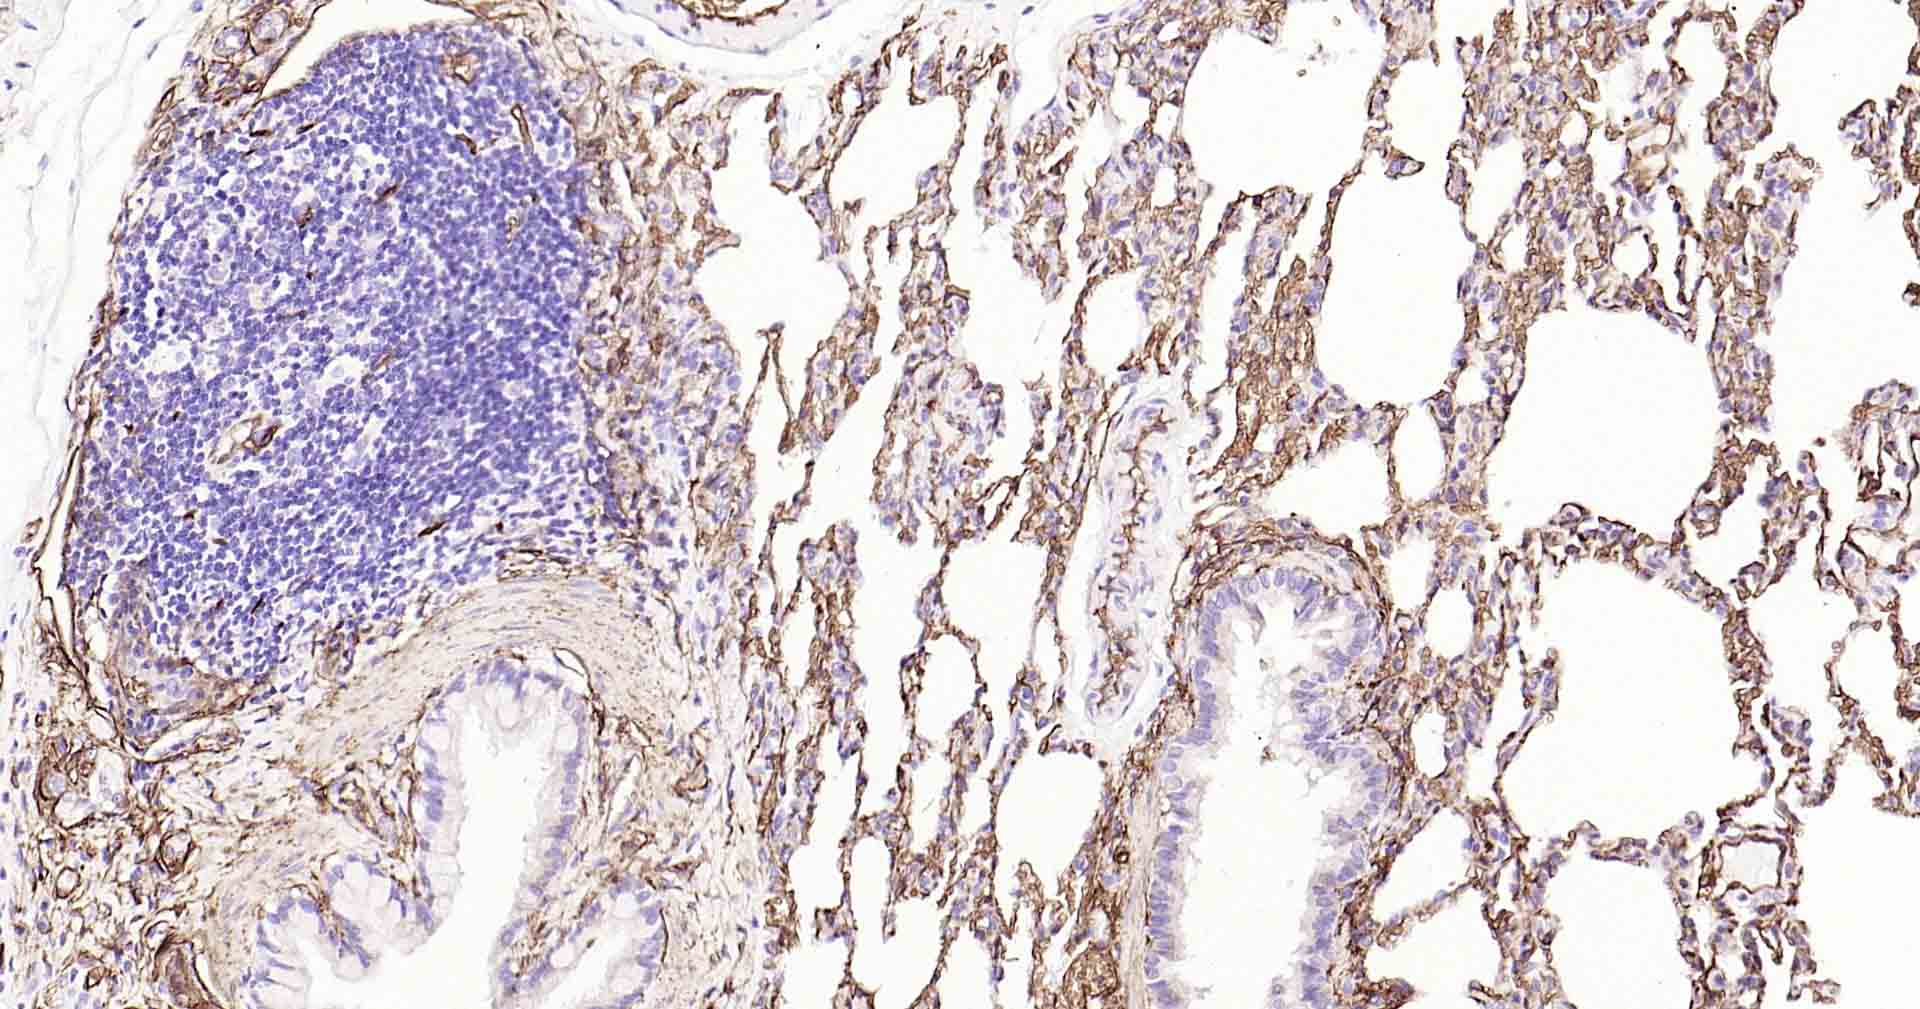

Paraformaldehyde-fixed, paraffin embedded Human Lung; Antigen retrieval by boiling in sodium citrate buffer (pH6.0) for 15 min; Antibody incubation with AQP1 Monoclonal Antibody, Unconjugated(bsm-52909R) at 1:200 overnight at 4°C, followed by conjugation to the SP Kit(Rabbit, SP-0023) and DAB (C-0010) staining.

Paraformaldehyde-fixed, paraffin embedded Rat Lung; Antigen retrieval by boiling in sodium citrate buffer (pH6.0) for 15 min; Antibody incubation with AQP1 Monoclonal Antibody, Unconjugated(bsm-52909R) at 1:200 overnight at 4°C, followed by conjugation to the SP Kit(Rabbit, SP-0023) and DAB (C-0010) staining.

Paraformaldehyde-fixed, paraffin embedded Mouse Lung; Antigen retrieval by boiling in sodium citrate buffer (pH6.0) for 15 min; Antibody incubation with AQP1 Monoclonal Antibody, Unconjugated(bsm-52909R) at 1:200 overnight at 4°C, followed by conjugation to the SP Kit(Rabbit, SP-0023) and DAB (C-0010) staining.